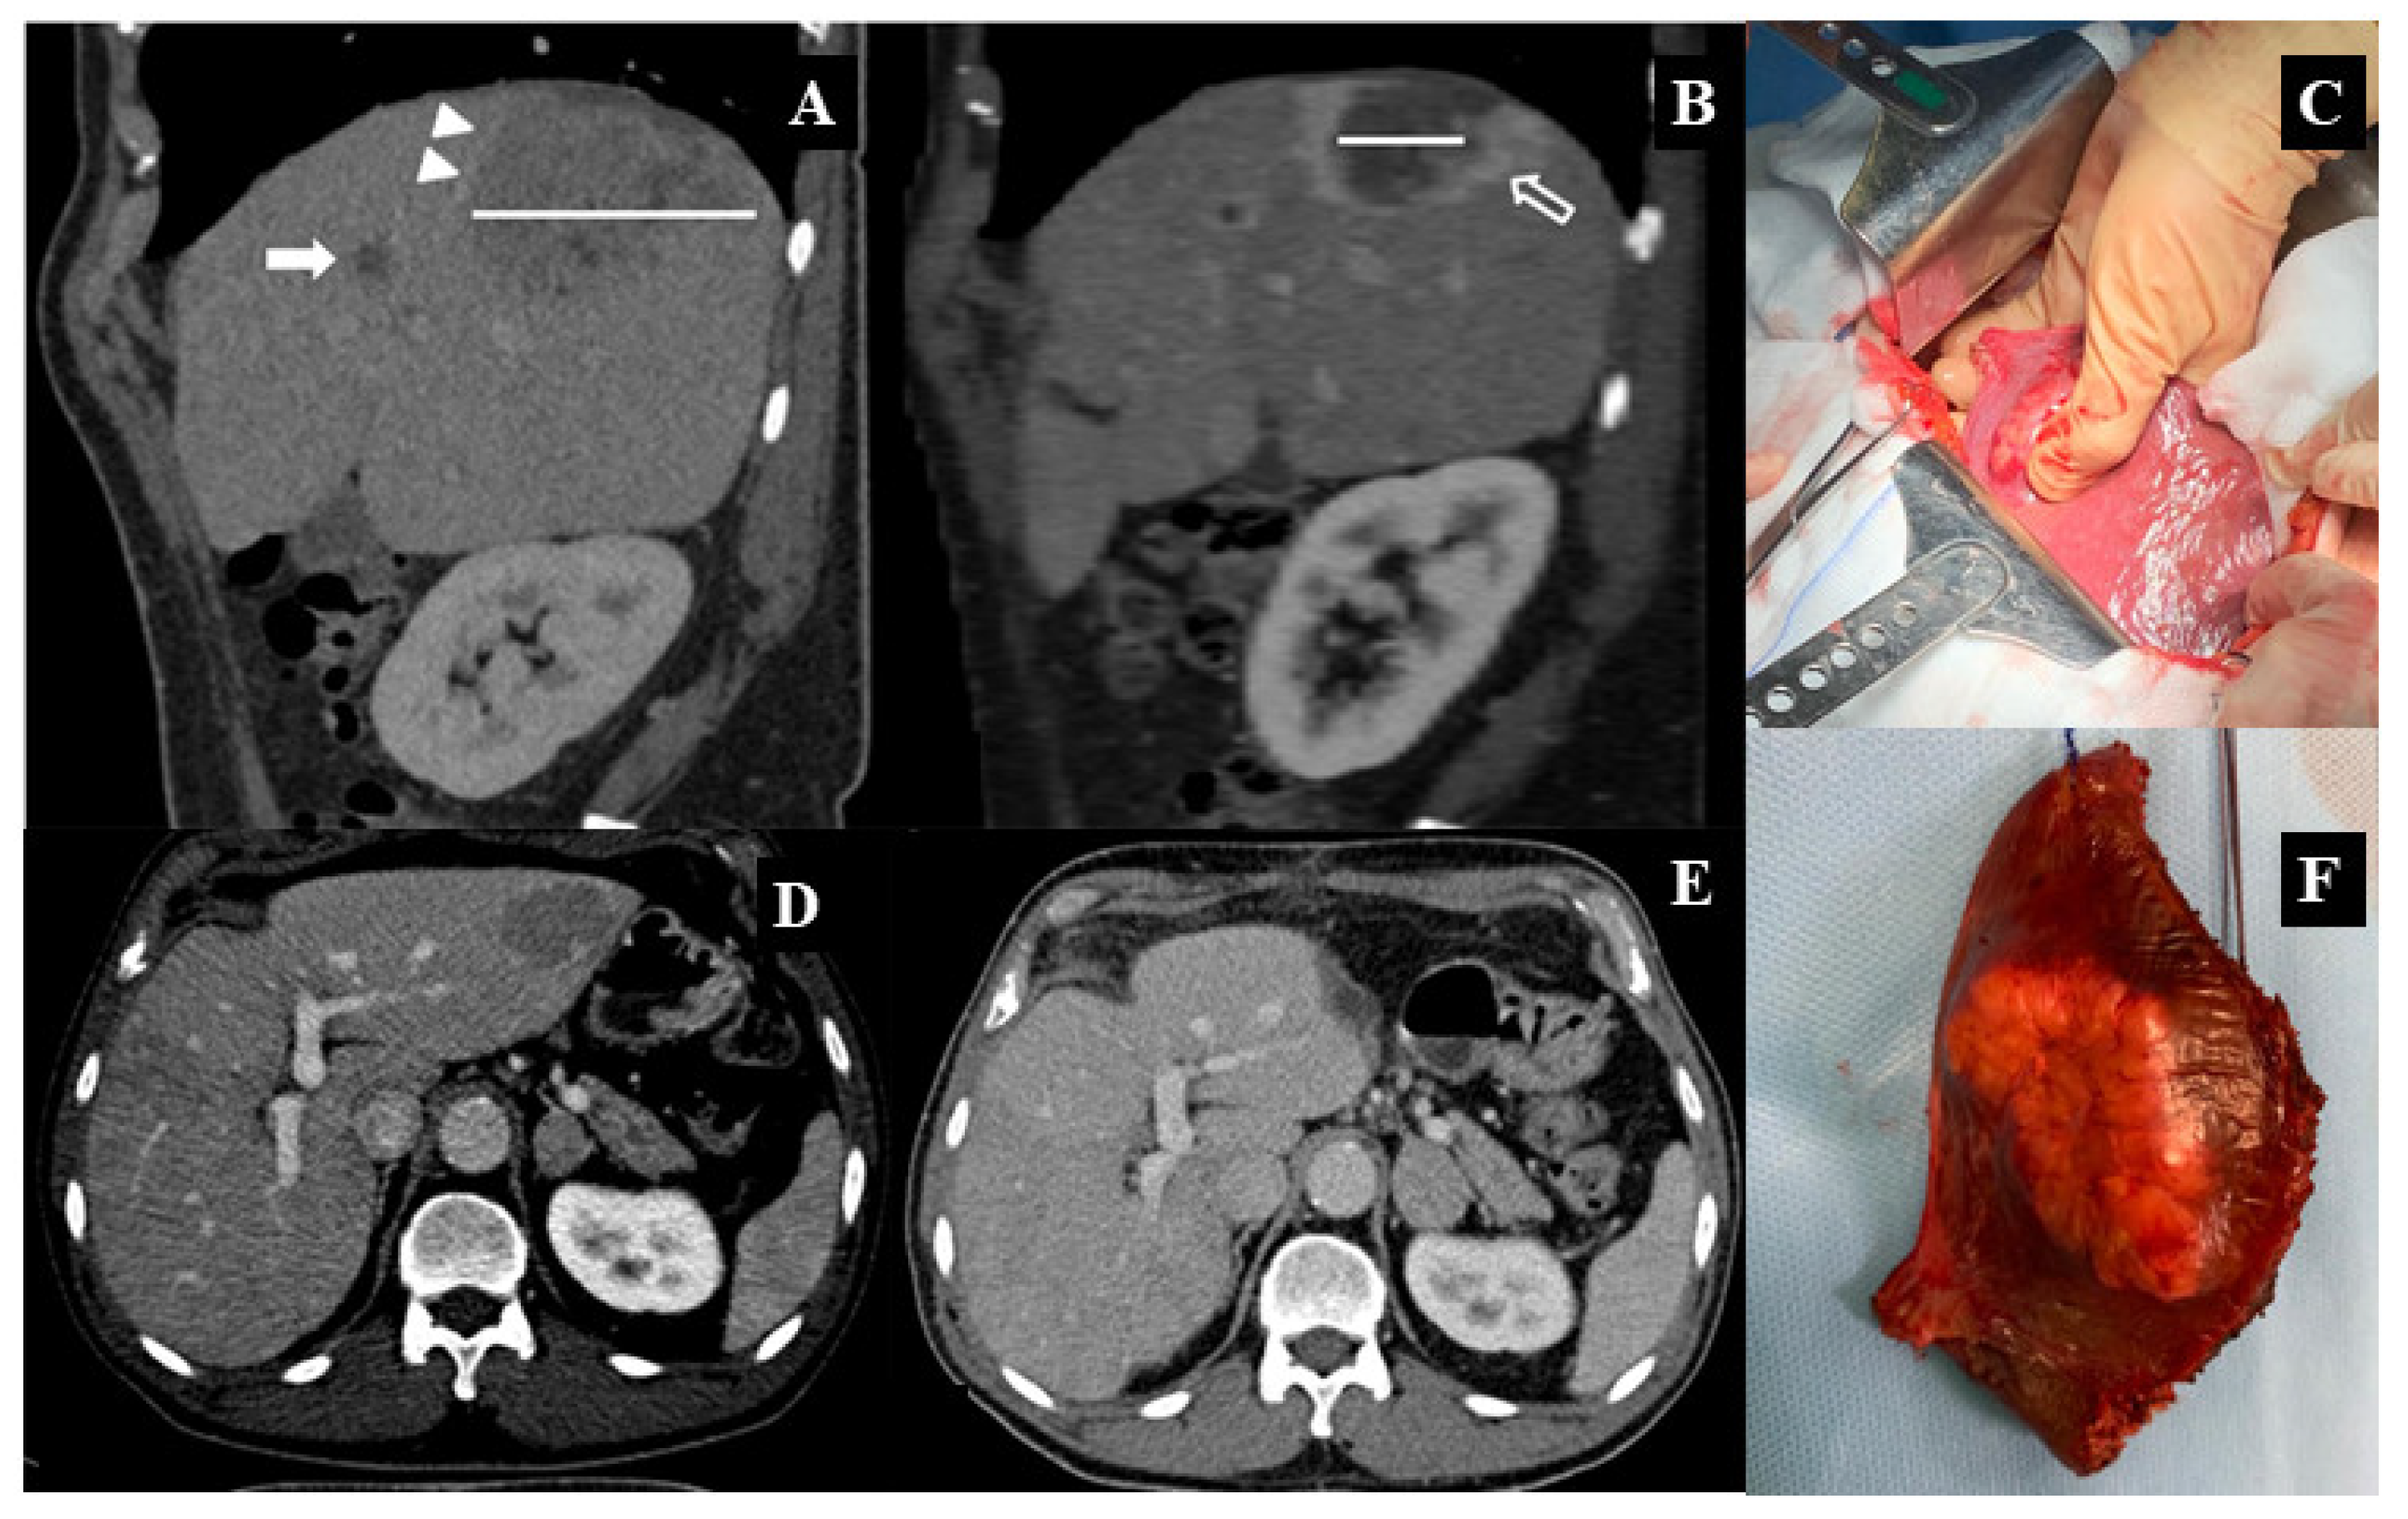

- Brozzetti, S.; Bini, S.; Fazzi, K.; Chiarella, L.L.; Ceccarossi, V.; De Lucia, C.; De Toma, G. Case-report: Metastases in a low-stage middle-graded HCC in cleared HCV infection, non-cirrhotic liver: Surgical therapy. Int. J. Surg. Case Rep. 2018, 47, 19–21. [Google Scholar] [CrossRef] [PubMed]